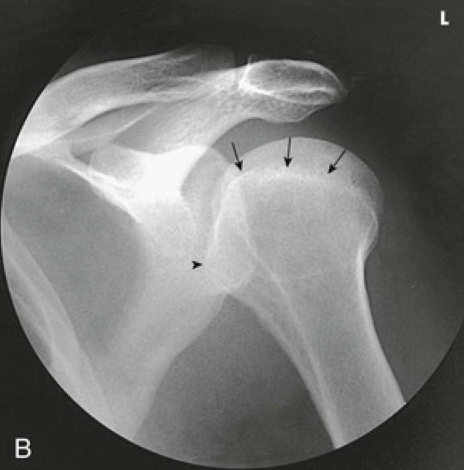

Question 5

Question

Label the image

Image:

2a7f2f74-1bbf-4ace-aca9-e4499490018d (image/png)

Answer

greater tubercle

lesser tubercle